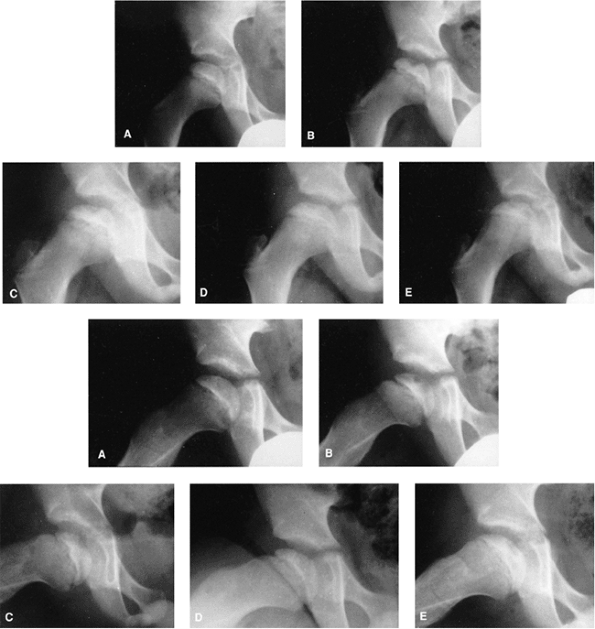

Figure 25.20 Anteroposterior (top, A–E) and lateral (bottom, A–E) views of a 7-year-old boy who presented with hip pain and a limp. A: At presentation, the patient was in the initial radiographic stage of the disease; his prognosis was indeterminate. B:

Six months after presentation, he had minimal loss of height of the lateral pillar and some radiolucency in that region, as well as significant bone resorption centrally. Note how the lateral pillar maintains its height throughout the course of the disease. C–E: One year (C), 18 months (D), and 3 years (E) after onset of disease. The patient had only mild symptoms on occasion, and maintained good range of motion throughout the course of the disease. Only symptomatic treatment was provided. |